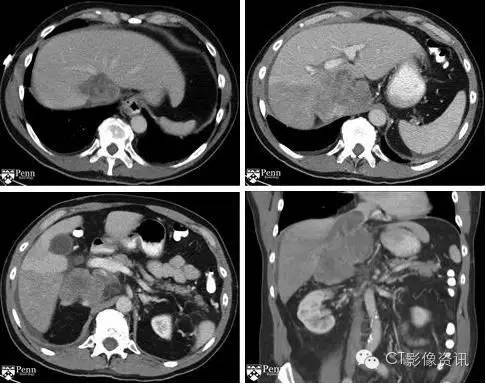

1. 肝脏可见“爪形征”? 2. 肿块位于下述哪个部位? 下腔静脉 62票 72% 肝脏 18票 21% 右心房 1票 1% 胰腺 5票 6%

3. 血栓延伸至以下哪个部位? 肝左静脉 7票 8% 肝中静脉 5票 6% 肝右静脉 46票 53% 以上都是 28票 33%

下腔静脉肝内段区域可见一巨大异源性肿块。血栓延伸至右心房及肝右静脉,造成肝右叶后段灌注异常。

最终诊断:腹膜后肉瘤 该患者行CT引导下穿刺,手术病理显示恶性平滑肌肉瘤。

下腔静脉平滑肌肉瘤要点 平滑肌肉瘤是最常见的累及下腔静脉的原发性恶性肿瘤。 它起源于血管壁平滑肌细胞。 下腔静脉平滑肌肉瘤好发于女性。 2/3的肿瘤以腔外生长为主,1/3肿瘤向腔内生长。 腔内肿瘤会引起静脉梗阻。 影像学上肿块常表现为下腔静脉内的充盈缺损,病变呈不均匀强化,有时伴有囊性坏死。 外生性肿瘤常常侵犯邻近组织,需要与直接起源于周围器官或者腹膜后的肿瘤鉴别。 腔静脉管腔的一个细微征象提示为下腔静脉来源。注意此细微征象为如果腔静脉管壁被压迫,或者与肿块接触面最大的下腔静脉如被压迫以致看不见。 下腔静脉的受累范围是很重要的,因为肿瘤常常侵犯肾静脉和肾上腺静脉,而这个是判断肿瘤预后的最重要因素。 下腔静脉肝内段受累被认为预后最差。 治疗需要完全手术切除,包括下腔静脉切除及随后的下腔静脉移植。